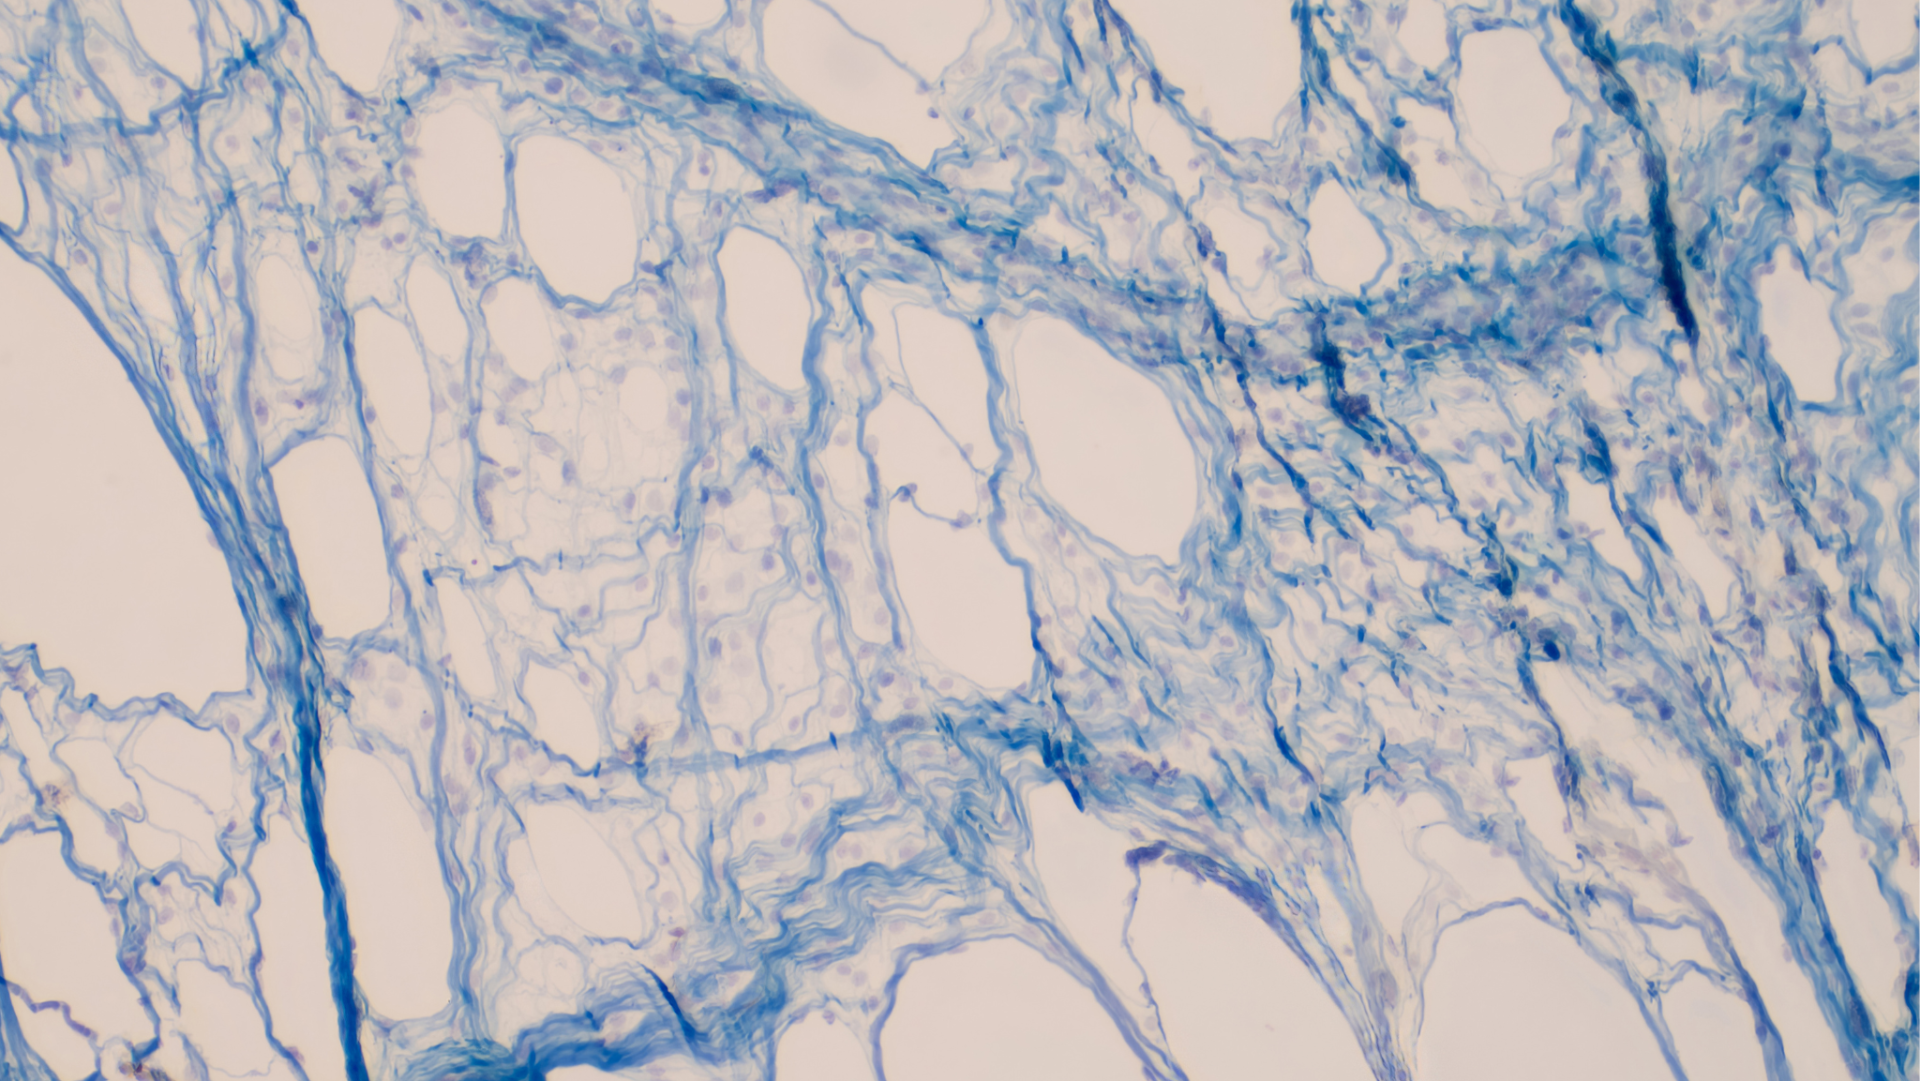

Bindweefseltechnieken

Bindweefsel technieken: Verhoog je doorbloeding en bewegingsvrijheid met fascia-tools.